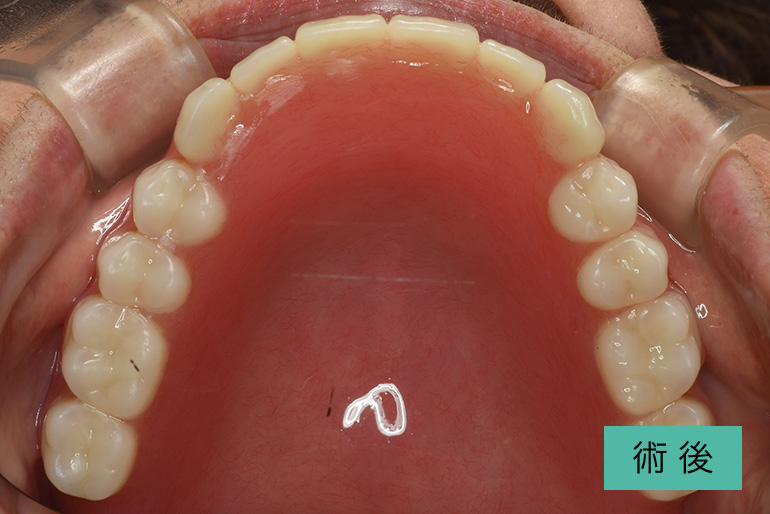

インビザライン③

| 治療内容 | 歯並びをキレイにしたい。 口腔内容積を狭くしないように、歯列を拡大し非抜歯で矯正をする。 |

|---|---|

| 治療期間・回数 | 約6年、80回 |

| 費用(税込) | ¥880,000(マウスピース矯正) ¥620,000(セラミッククラウン) ※自由診療 |

| リスク・副作用 | 歯肉退縮、知覚過敏、後戻り |